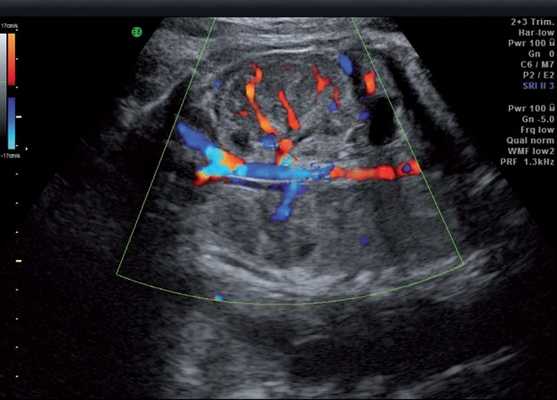

Результаты исследования: размеры плода пропорциональные, соответствуют менструальному сроку беременности. При эхокардиографии особенностей строения сердца у плода не выявлено. При оценке органов мочевыделительной системы обнаружено следующее: правая почка плода нормальных размеров и структуры. Левая почка увеличена до размеров 53х38х46 мм при 95-м процентиле нормативных для срока значений 43х24х23 мм [4] (рис. 1). В структуре почки, преимущественно в верхнем и среднем сегментах, определяется округлое образование без четких контуров, средней эхогенности, приблизительные размеры его 50х35х35 мм. При цветовом допплеровском картировании в образовании визуализируется обширная сосудистая сеть. При допплерометрии индексы сосудистой резистентности (рис. 2) в разных участках образования варьируют в широких пределах (от 0,49 до 0,77).

Рис. 2. Режим цветового допплеровского картирования. Хорошо видны различия в характере васкуляризации нормальной почки и контрлатеральной пораженной почки.

Мезобластическая нефрома - это односторонняя округлая солидная опухоль без капсулы, однородной структуры, иногда содержащая кистозные включения, образующиеся за счет кровоизлияний или очагов некроза. Микроскопически опухоль представлена мезенхимальными клетками, к которым относятся гладкие мышечные волокна и незрелые фибробласты. Кроме того, она может содержать клеточные элементы почечных клубочков и трубочек. Эта опухоль не имеет капсулы и способна к инфильтрирующему росту. Опухоль хорошо васкуляризирована и имеет развитую сосудистую сеть [4].

При ультразвуковом исследовании опухоль Вильмса также выглядит как округлое, хорошо отграниченное образование средней эхогенности. При цветовом допплеровском картировании выраженной сосудистой сети обычно обнаружить не удается. Экстраренальные сочетанные аномалии развития при нефробластоме встречаются редко [9, 10].

В представленном клиническом наблюдении диагноз опухоли почки был поставлен нами практически сразу и не вызывал сомнения, поскольку стандартный протокол ультразвукового скринингового исследования во II и III триместрах беременности требует описания почек и мочевого пузыря. Почки оцениваются в поперечном и продольном сечениях с использованием при необходимости цветового допплеровского картирования (рис. 3, а, б). В данном случае почки плода располагались в типичном месте, но обращали на себя внимание значительная разница в размерах и необычная структура одной из почек (см. рис. 1). В 2D режиме границы опухоли четко не визуализировались, но при использовании технологии VCI (объемное контрастное изображение) можно было более точно определить ее контуры (рис. 4).